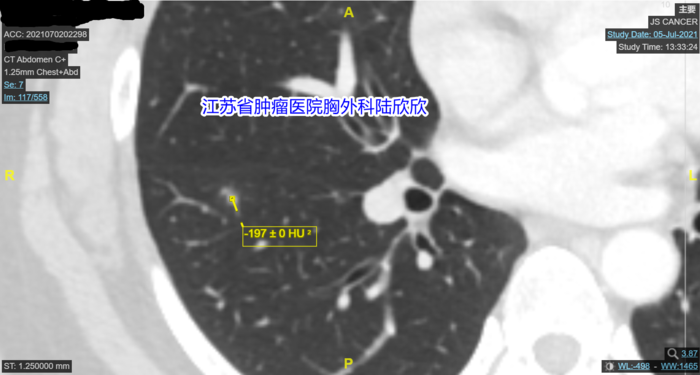

最大CT值-192的图我一时找不到了。我下面有两张图。最大CT值是-197和-212,和-192已结很接近了。

我再观察,发现结节的外形有点不规则,这也是肺癌的一个表现。我测量了磨玻璃结节内部多点的CT值,我说:“你的结节最大CT值是-192,磨玻璃结节周围有环状强化,内部有点状实性成分。所以这个混合磨玻璃结节不可能是原位癌,磨玻璃结节如果是原位癌的话,密度很均匀,一般没有实性成分,形状接近于球形。你的磨玻璃结节密度不均匀,而且有点状实性成分,局部形状不规则,所以可以排除原位癌。那么有没”有可能是微小浸润性腺癌呢?最大CT值我测给你看,大约-192。磨玻璃结节中微小浸润性腺癌的CT值要高一些,一般在-560到-460之间。磨玻璃结节中浸润性腺癌的CT值要更高一些,一般在-460以上,平均值-260左右你的磨玻璃结节最大CT值我刚才测量了,大约-192,CT室医生测量平均CT值-378,所以这个磨玻璃结节应该超过了微小浸润性腺癌的阶段,现在估计已经到了浸润性腺癌的阶段。所以,我的结论和省人民医院和我们医院影像科的看法不一样,他们都认为很可能是微小浸润性腺癌,我认为最可能的诊断是浸润性腺癌。当然也不能排除炎性病变,不过可能性很小。另外,这个结节贴近肺裂胸膜,如果是恶性的磨玻璃结节,比较危险,将来有侵犯胸膜的危险。最好手术切除。手术可以基本上治愈。